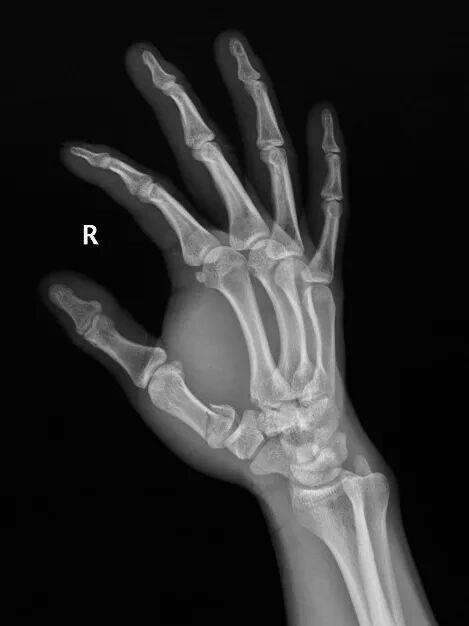

患者是52歲男性,因摔倒導致右手第一掌骨基底部骨折

手術前右手正斜位片